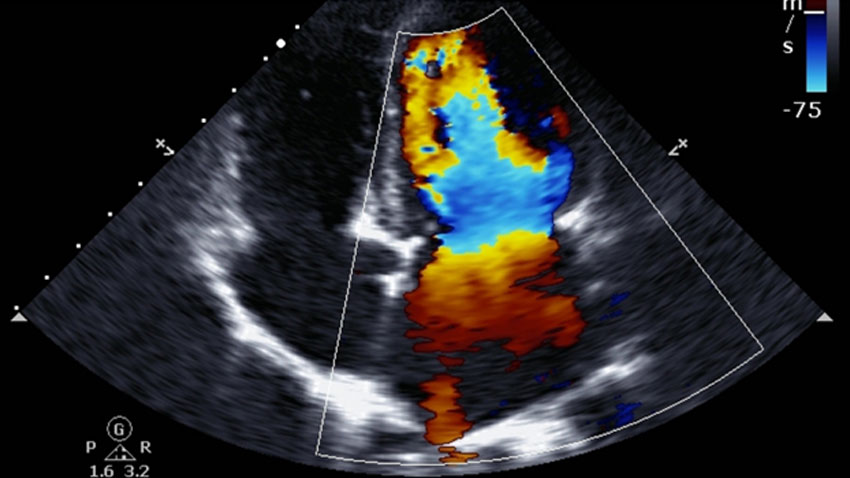

Color Doppler

Colour Doppler is a medical imaging technique utilized to offer visualization of the blood flow by using color processing to add color in the image so that a doctor can see what is happening inside the body.